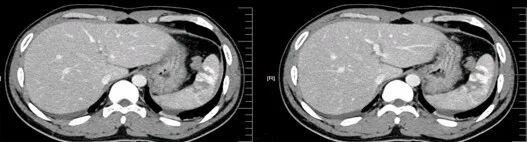

CT表现:

对于肝损伤CT能确定其存在及范围,且有非常高的特异性。肝包膜下血肿会形成新月形或半月形的低密度或等密度区,相应的肝实质会受压变平而显示肝表面的边界失去正常的弧形而变平,尤其血肿新鲜时其CT值与肝实质类似,此时注意肝表面周缘的改变亦就显得重要。

一般来讲,血肿的CT值随时间的推移而减低。在肝实质的血肿则常常显示圆形、卵圆形或星状低密度影。肝撕裂会见到单一或多发的线样低密度,边缘模糊。